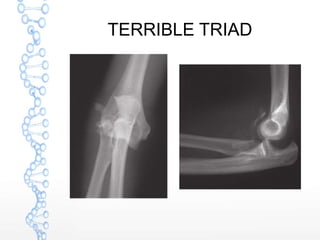

TERRIBLE TRIAD